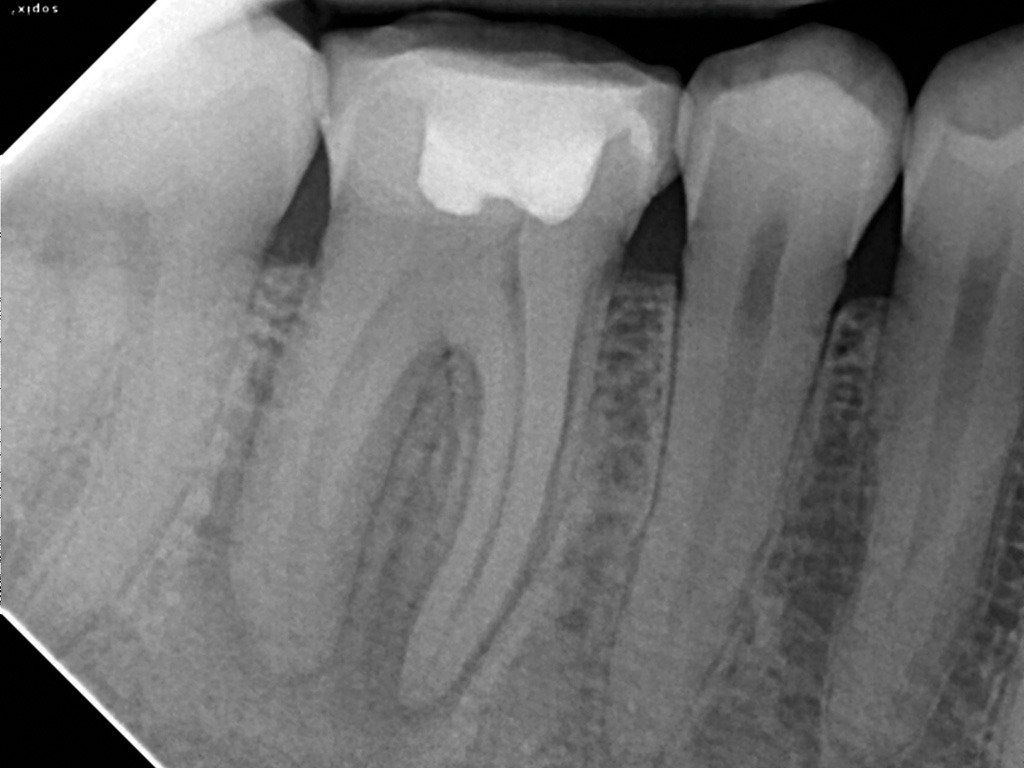

A radiologia odontológica digital oferece uma série de benefícios as pessoas e profissionais. Ela dispensa filmes radiográficos, oferece maior precisão em resultados, armazenamento de arquivos digitais com mais praticidade, que pode ser retirada através da internet ou por e-mail, menor exposição à radiação, e maior agilidade. Ao contrário da radiografia, que precisa ser revelada, a radiologia digital envia diretamente a imagem para o computador, deixando o processo de diagnóstico mais ágil, sem necessidade de esperar alguns dias para o exame ficar pronto.